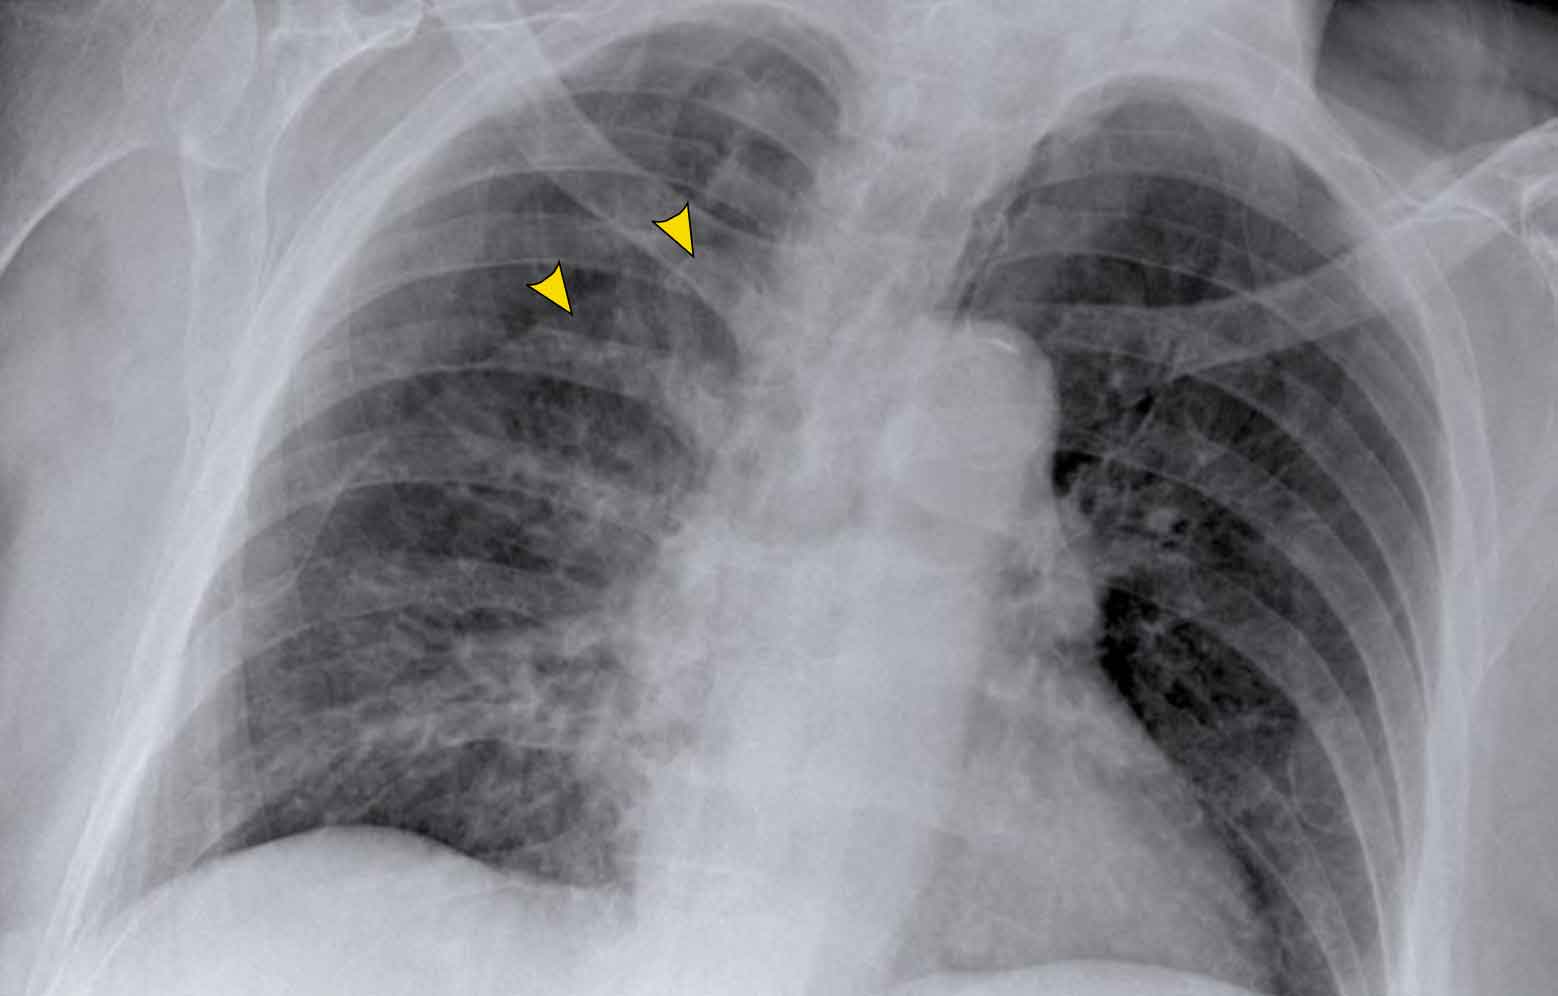

Displacement of the Azygoesophageal Line (1) – Hiatal hernia

A hiatal hernia (arrowheads) is the most common cause of displacement of the azygoesophageal line as seen on the PA-view.

Notice the air within the hernia on the lateral view (black arrow).